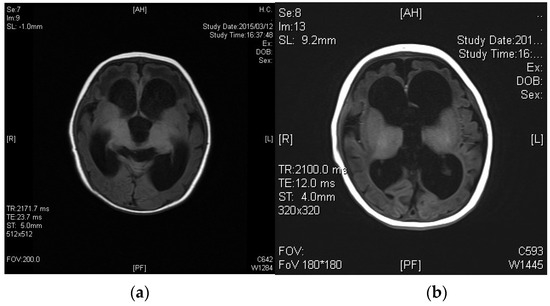

Figure 3.

Brain CT of Case 2 at 12 months of age, 7 months after starting betaine treatment.

The administration of betaine monohydrate (100 mg/kg/day) was started at 4 months of age, and her respiratory status and vitality improved rapidly. Sanger sequencing of the methylenetetrahydrofolate reductase gene (MTHFR) detected a homozygous variant, c.466_467GC > TT, and both parents were found to be heterozygous carriers of this variant. Based on the diagnosis of homocystinuria type III caused by MTHFR deficiency, betaine therapy was continued at the dosage of 300 mg/kg/day, which raised plasma Met levels to 14–40 μmol/L, and reduced plasma tHcy concentrations to 50–110 μmol/L. Head MRI at the age of 12 months revealed the almost complete resolution of ventricular enlargement and atrophic changes (Figure 3). However, severe psychomotor retardation became evident, with a development quotient of 36 at the age of 1 year and 4 months. Epileptic seizures also appeared at the age of 3 years, so the administration of sodium valproate was added. This case was reported previously [9].